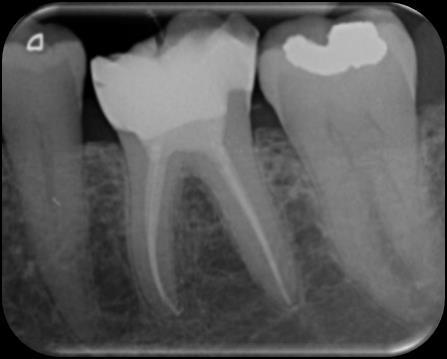

Dr. Dhiraj Arora: A Simple Sequence for Successful Root Canal Treatment Outcomes (EN)